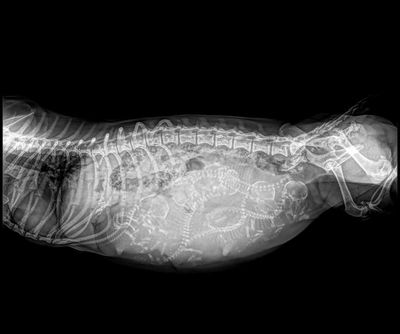

Each litter is carefully planned and pre-matched. Dam’s heat cycles are logged into a calendar which will generally last 21 days. If a mating will not occur then the dam is placed in quarantine. If a mating occurs, the sire is chosen based on their DNA compatability and experience together and puppies they may have already produced. Then that is logged into the calendar and 65 days are added for a possible birth. At day 55 the Dam is taken to the Vet for an X-Ray puppy count so I know how many puppies to expect and I’m not blind sighted.